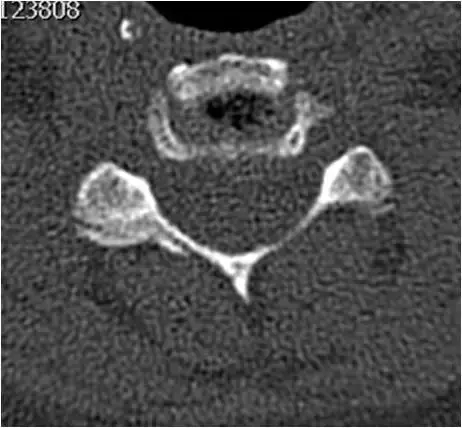

图21:颈椎中段的轴向截面。广泛的左钩椎关节肥大。左神经孔狭窄,出口神经根受压。

图22:颈椎中段的轴向截面。骨窗。与图像21相同的患者和相同的水平。广泛的左钩椎关节肥大。左神经孔狭窄,出口神经根受压。